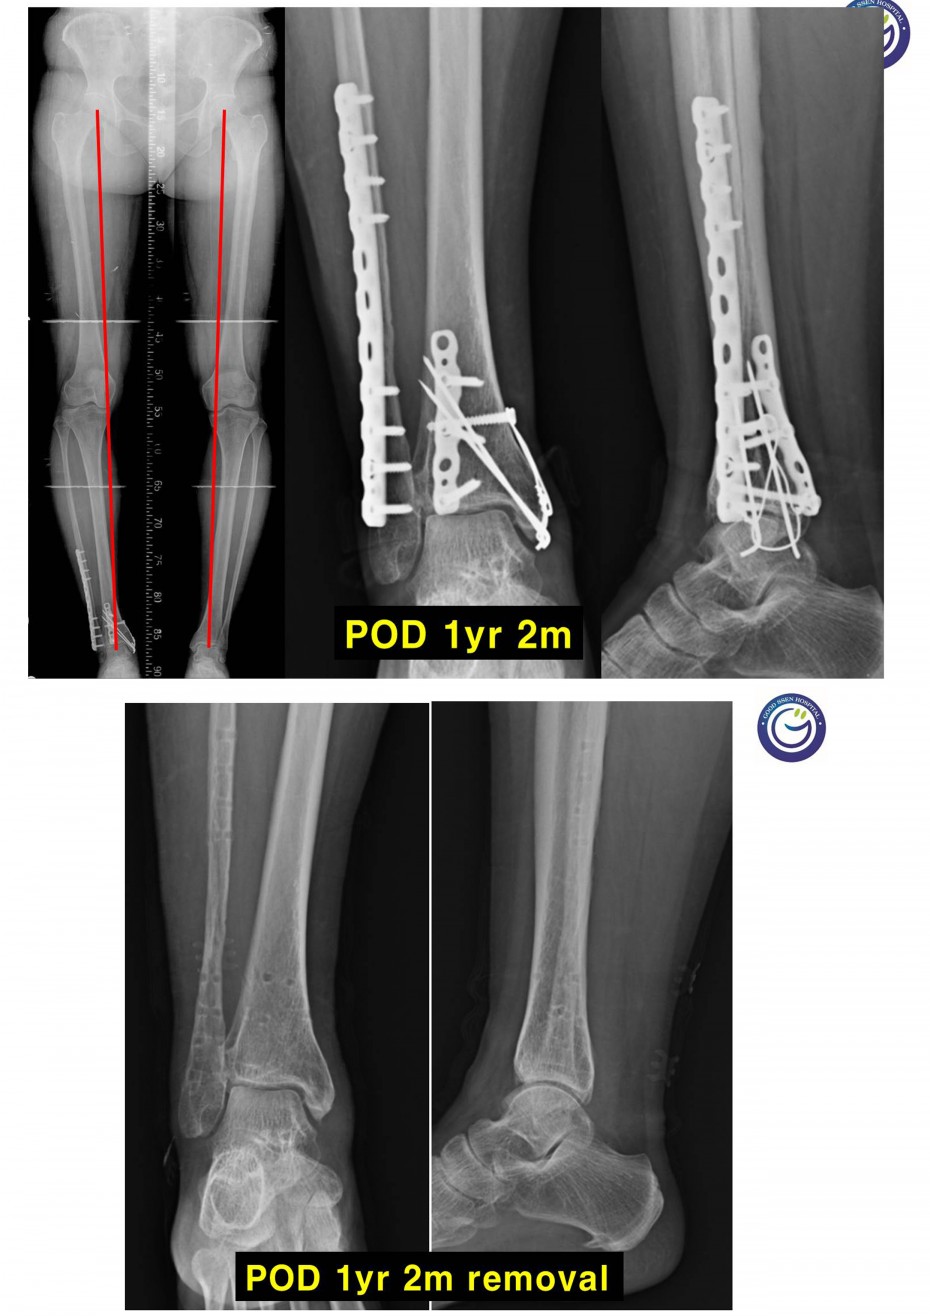

관절을 침범하는 심한 분쇄골절

절개없이 고정하는 최소침습적 고정방법 (MIPO)